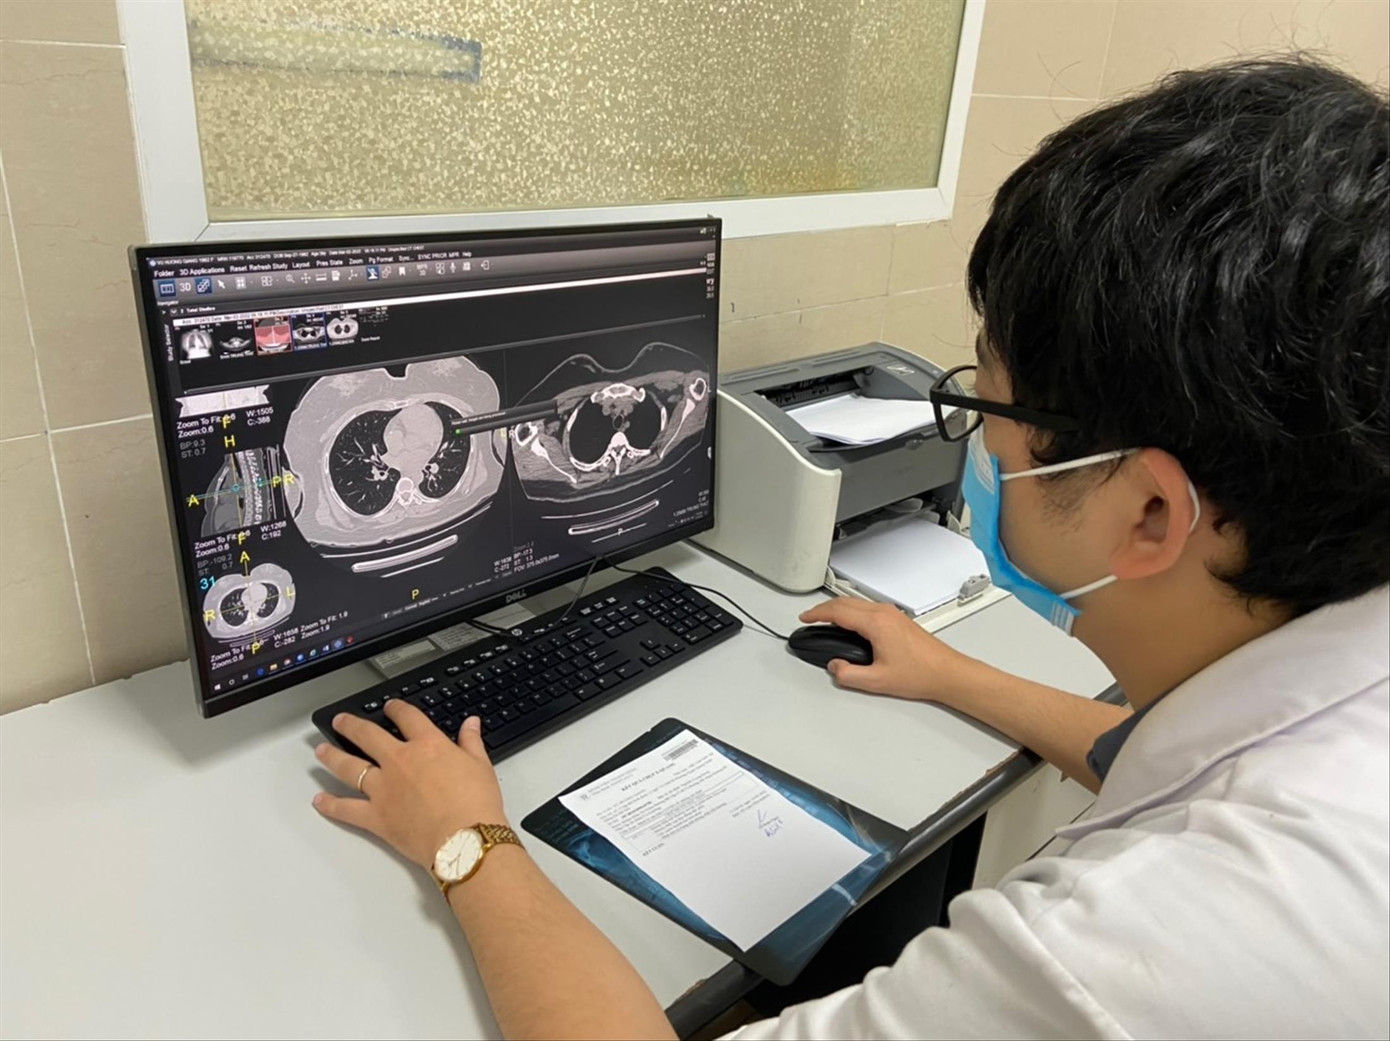

| Bác sĩ BV Thanh Nhàn kiểm tra phim chụp phổi của bệnh nhân COVID-19 |

PGS.TS Lương Ngọc Khuê cho biết tại Bệnh viện Bạch Mai, 50-60% những bệnh nhân sau mắc COVID-19 với triệu chứng hô hấp kéo dài đến khám được chụp X-quang hoặc chụp cắt lớp vi tính lồng ngực thấy có tổn thương; sốt nhẹ, khó thở, mệt mỏi, đau cơ, khớp, rụng tóc, xơ phổi, tim đập nhanh hoặc đánh trống ngực, rối loạn nội tiết, huyết học bị huyết khối…